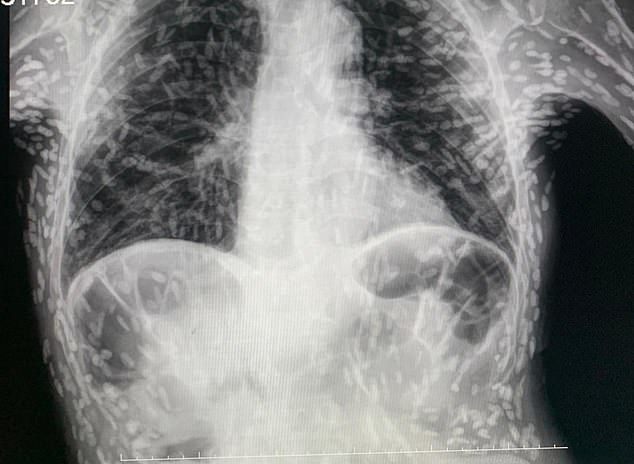

[서울=뉴시스]김경문 인턴 기자 = 지속적으로 기침을 하며 고통을 호소하던 한 환자의 엑스레이(X-ray) 검사 결과 복부에 수백 마리의 기생충이 가득 차 있었다.

지난 4일(현지시간) 영국 데일리메일은 브라질의 한 의료진이 자신의 소셜미디어에 이 같은 엑스레이 사진을 공유했다고 보도했다. 이 사진에는 환자의 몸 곳곳 수백 개의 점 형상이 있었다. 각각의 점은 석회화(혈액 중 칼슘이 축적되는 것) 된 기생충 사체였다.

이 사진을 공개한 브라질 의료진은 환자가 별다른 치료가 필요하지 않다고 했다.

의료진은 "머리, 척수, 눈 등에 이상이 생긴 것이 아니면 치료를 받을 필요가 없다"며 "이미 석회화되었기 때문에 살아있는 유충이 아니어서 특별한 조치가 필요하지 않다"고 밝혔다.

다만 이 환자는 현재 뇌에도 낭종이 있는지 확인하기 위해 자기공명영상(MRI) 검사를 기다리고 있는 것으로 알려졌다.